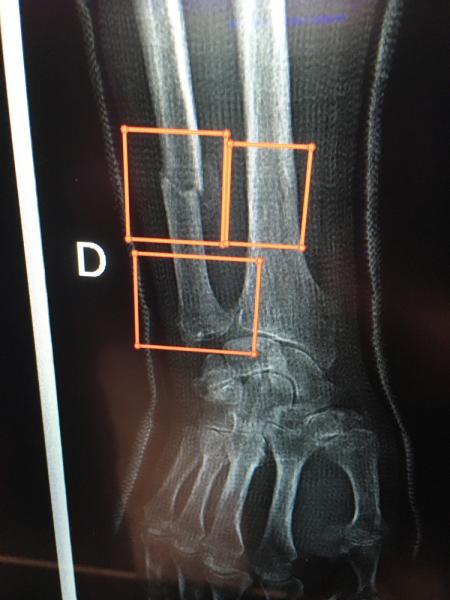

Here are images of some of the newest new medical imaging technologies displayed on the expo floor at the Radiological Society of North America (RSNA) 2019 meeting. Use the slider images below to see the photos.